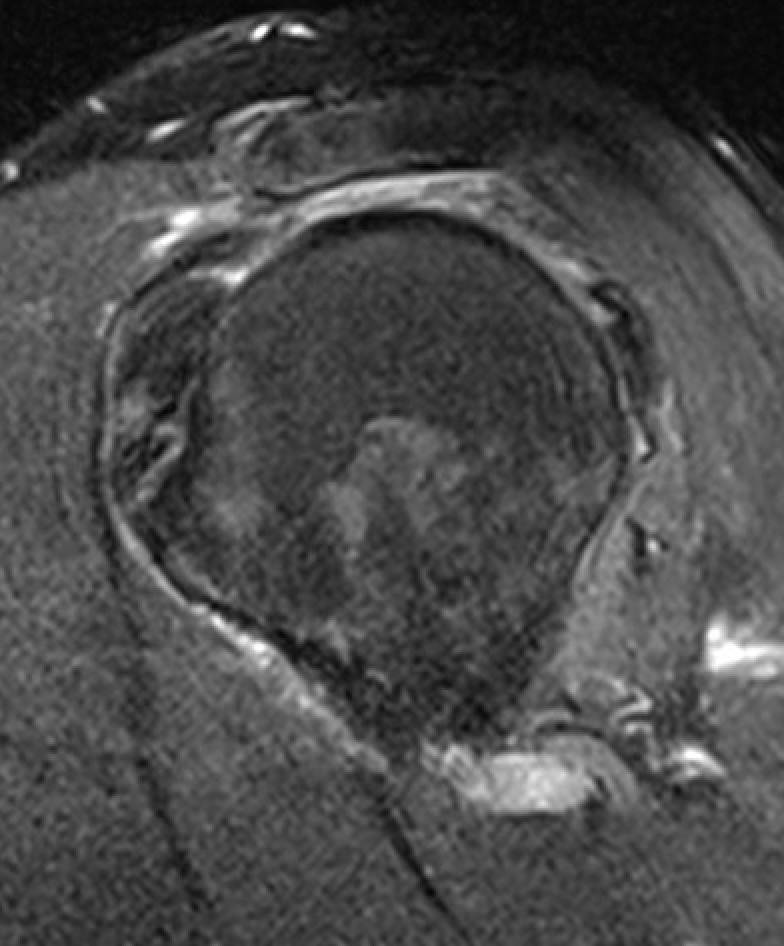

Goutallier classification

Amount of fatty degeneration in rotator cuff muscle belly on a T1 sagittal MRI

Stage 0: normal muscle

| Stage 1 | Stage 2 |

Some fatty streaks MRI shows some fatty streaks in supraspinatus |

More muscle than fat MRI shows grade 2 in supraspinatus |

Equal fat and muscle MRI demonstrates grade 3 supraspinatus and infraspinatus |

More fat than muscle MRI demonstrates grade 4 infraspinatus |